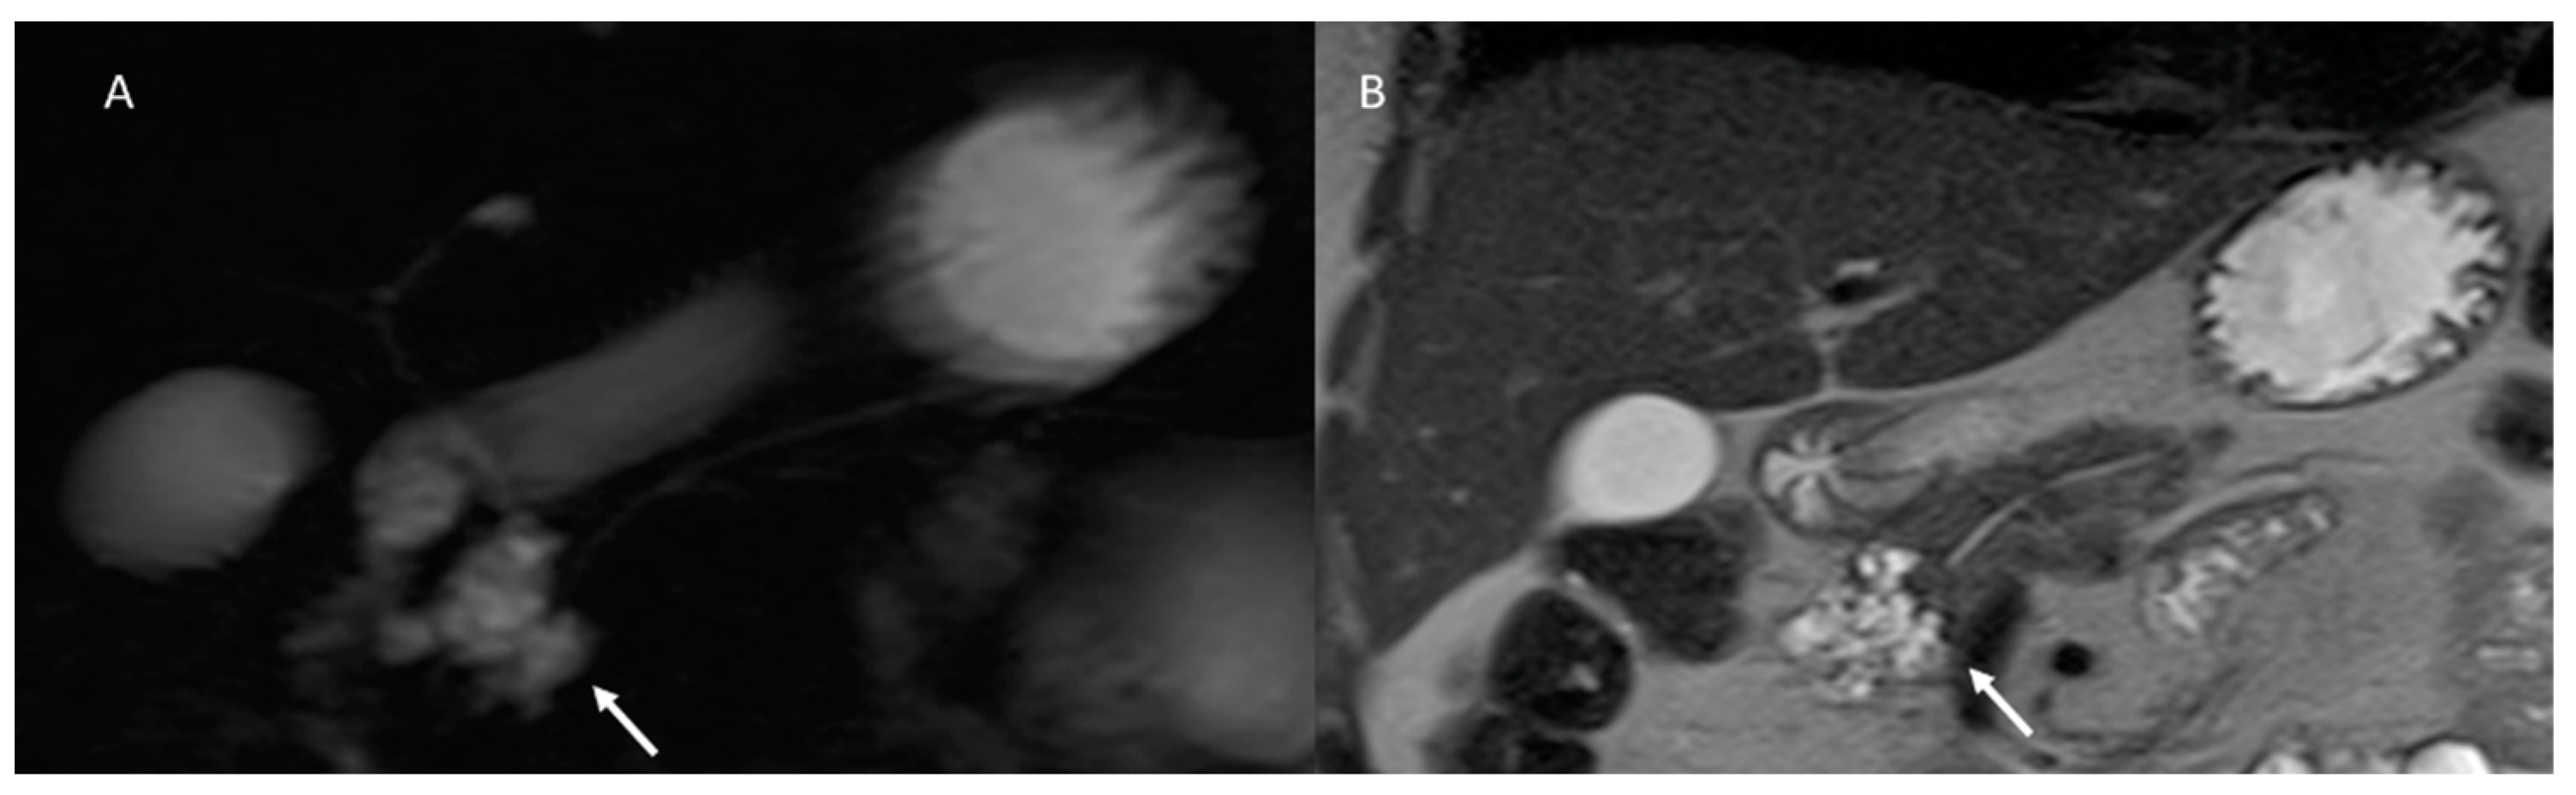

- Hecht, E.M.; Khatri, G.; Morgan, D.; Kang, S.; Bhosale, P.R.; Francis, I.R.; Gandhi, N.S.; Hough, D.M.; Huang, C.; Luk, L.; et al. Intraductal papillary mucinous neoplasm (IPMN) of the pancreas: Recommendations for Standardized Imaging and Reporting from the Society of Abdom.inal Radiology IPMN disease focused panel. Abdom. Radiol. 2020, 46, 1586–1606. [Google Scholar] [CrossRef] [PubMed]

- Yoon, J.G.; Smith, D.; Ojili, V.; Paspulati, R.M.; Ramaiya, N.H.; Tirumani, S.H. Pancreatic cystic neoplasms: A review of current recommendations for surveillance and management. Abdom. Radiol. 2021, 46, 3946–3962. [Google Scholar] [CrossRef]

- Sainani, N.I.; Saokar, A.; Deshpande, V.; Castillo, C.F.-D.; Hahn, P.; Sahani, D.V. Comparative Performance of MDCT and MRI With MR Cholangiopancreatography in Characterizing Small Pancreatic Cysts. Am. J. Roentgenol. 2009, 193, 722–731. [Google Scholar] [CrossRef]

- Waters, J.A.; Schmidt, C.M.; Pinchot, J.W.; White, P.B.; Cummings, O.W.; Pitt, H.A.; Sandrasegaran, K.; Akisik, F.; Howard, T.J.; Nakeeb, A.; et al. CT vs. MRCP: Optimal Classification of IPMN Type and Extent. J. Gastrointest. Surg. 2007, 12, 101–109. [Google Scholar] [CrossRef]

- Pilleul, F.; Rochette, A.; Partensky, C.; Scoazec, J.-Y.; Bernard, P.; Valette, P.-J. Preoperative evaluation of intraductal papillary mucinous tumors performed by pancreatic magnetic resonance imaging and correlated with surgical and histopathologic findings. J. Magn. Reson. Imaging 2005, 21, 237–244. [Google Scholar] [CrossRef]